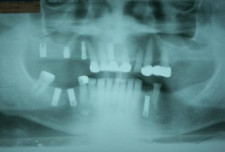

Implantes con el Muñón Protésico

Tornillos de Cicatrización

• En el lugar donde son colocados detienen la reabsorción del hueso alveolar.